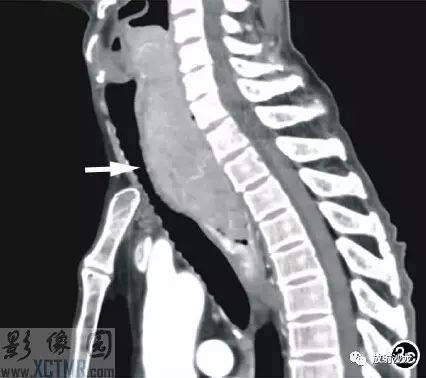

上消化道鋇餐:食管胸上段可見(jiàn)不規(guī)則充盈缺損,約5.6cm*4.2cm,黏膜結(jié)構(gòu)紊亂,管壁不規(guī)整,對(duì)比劑通過(guò)稍緩慢,會(huì)厭動(dòng)度不協(xié)調(diào),考慮食管癌(圖2)。CT:食管胸上段見(jiàn)軟組織腫塊,上自杓會(huì)厭披裂,下至主動(dòng)脈弓水平,腫塊邊緣清晰,密度均勻,增強(qiáng)掃描輕到中度不均勻強(qiáng)化,食管腔狹窄,氣管、右側(cè)甲狀腺、鄰近血管受壓移位(圖3),縱隔未見(jiàn)腫大淋巴結(jié),診斷:食管癌可能。

手術(shù)所見(jiàn):腫塊位于食管,約15cm*6cm,上界到喉甲狀軟骨氣管起始處,下達(dá)胸骨后,質(zhì)軟,與食管粘連緊密,周圍無(wú)明顯侵犯,無(wú)法完全切除,行活檢送病理檢查。病理:送檢組織切面呈魚(yú)肉狀;鏡下見(jiàn)腫瘤細(xì)胞彌漫排列,核大,深染,多圓形或不規(guī)則,部分核碎裂,胞漿淺淡,多少不等;免疫組化:S 100(-),HMB45(-),CK(-),CD3(-),CD20(+),CD45RO(-),CD79a(+),CD21散在(+),Mum-1(+),Bcl-2(-),Bcl-6(-)。診斷:(食管)非霍奇金B細(xì)胞淋巴瘤(圖4)。